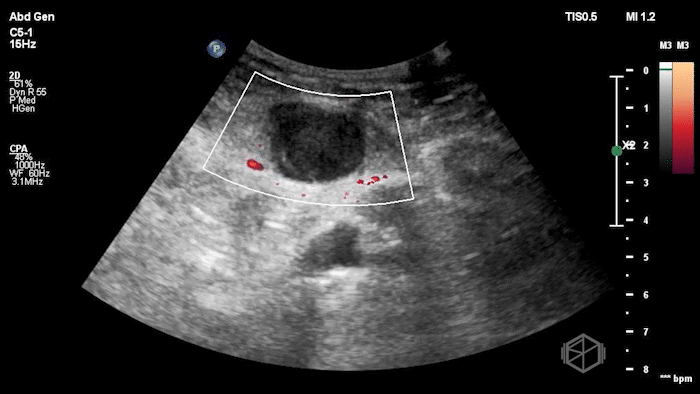

Given the patient’s focal abdominal wall tenderness, a POCUS exam of the left lower quadrant at the point of maximal pain was performed.

She obtained the following images:

The POCUS shows an hypoechoic circular mass within the rectus muscle. There is no active color doppler flow suggesting likely no active bleeding.

Diagnosis: Rectus sheath hematoma (RSH)